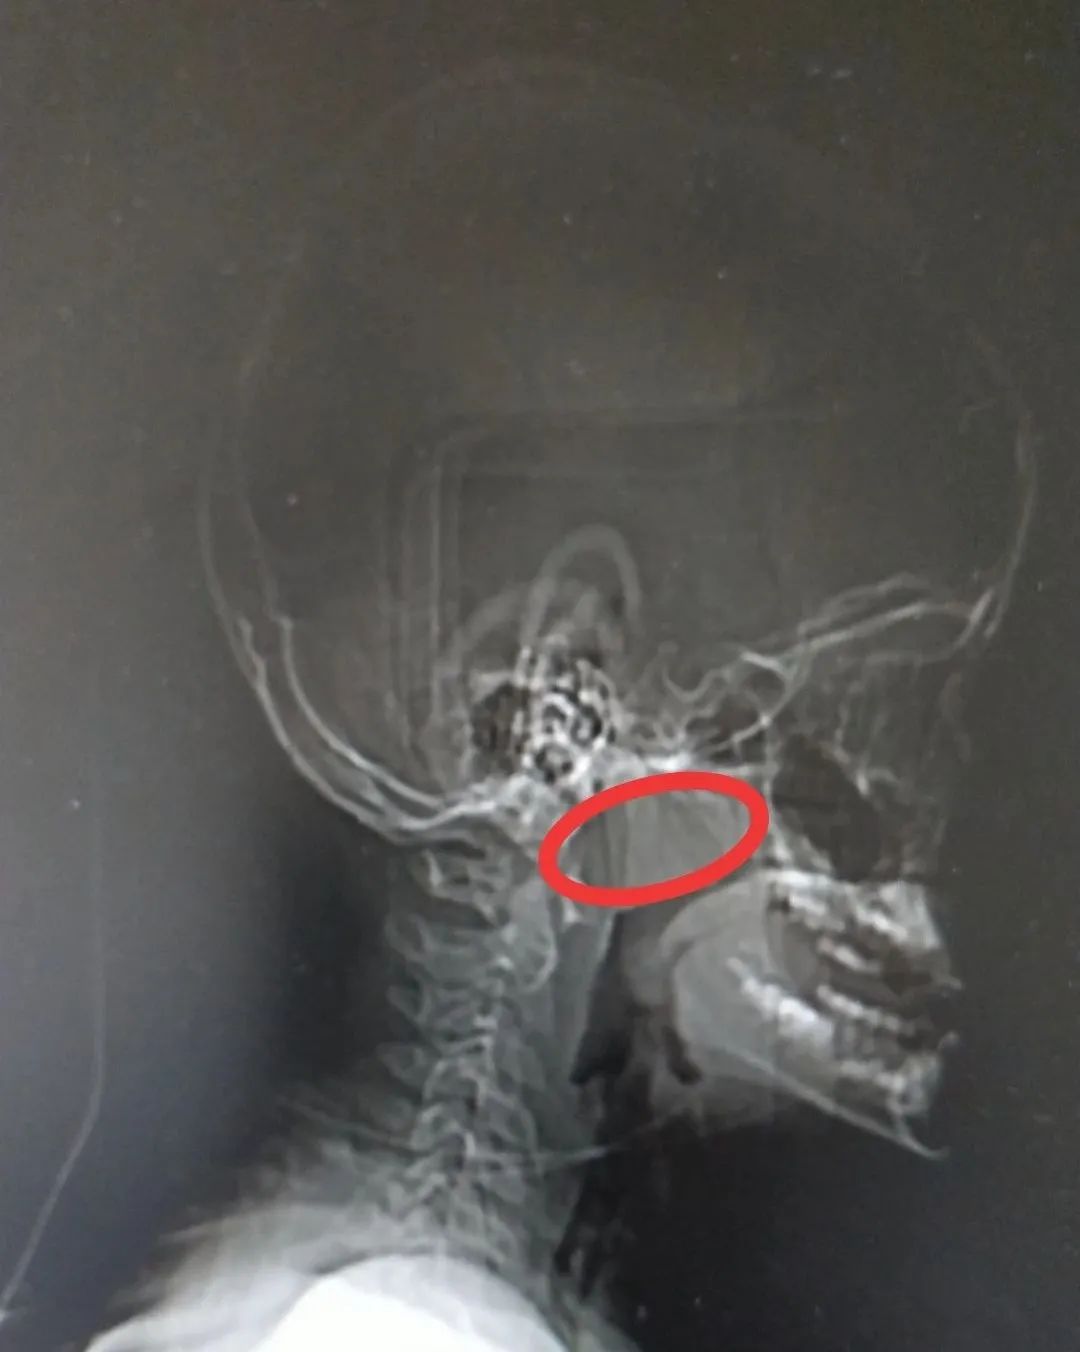

侧位片下呈现的腺样体,堵塞严重,达到了五分之四。